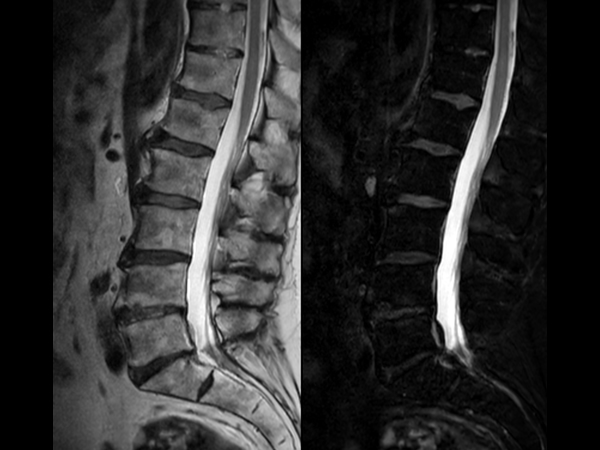

Comprehensive Lumbar Spine imaging at 3.0T